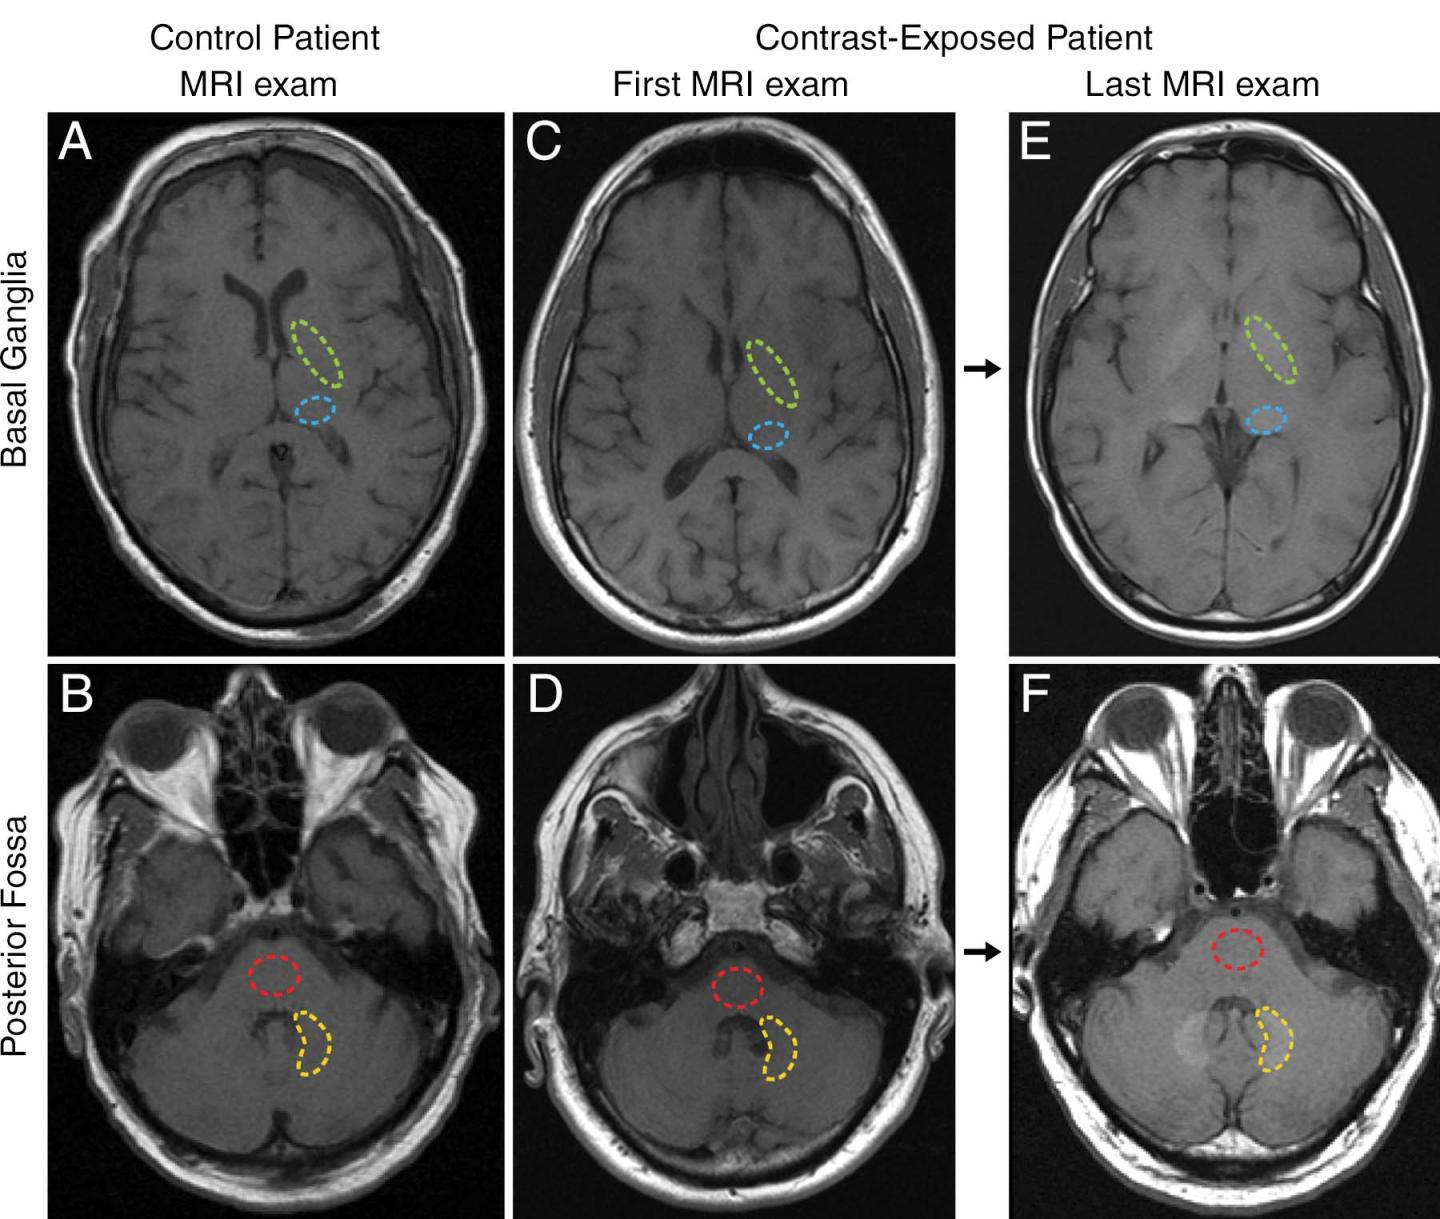

Scientists previously believed gadolinium contrast material could not cross the blood-brain barrier, the semipermeable membrane that selectively filters materials from the bloodstream from entering extracellular fluid in the brain and central nervous system. However, recent studies, including one from Dr. McDonald and colleagues, found that traces of gadolinium could be retained in the brain for years after MRI.

For this study, Dr. McDonald and colleagues set out to identify the neurotoxic potential of intracranial gadolinium deposition following intravenous administration of gadolinium-based contrast agents during MRI.